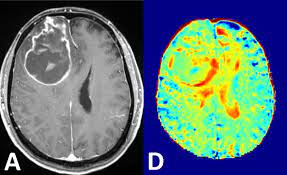

Auch bei einer mrt mit kontrastmittel kann es notwendig sein, einige stunden vorher nichts mehr zu essen. Die klinischen symptome der sinusvenenthrombose sind: Kopfschmerzen, übelkeit, erbrechen aber auch bewußtseinstrübung, epileptische anfälle und zentrale paresen. Und zwar vor einer sinusvenenthrombose. Welche risikogruppen mit welchen risikofaktoren gibt es?

Ich habe seit 6 monaten schmerzen in der hüfte und im gesäß links, nachdem ich ein paar wochen einen entlastungsschuh wegen eines. Hallo, ich bekomme ein mrt meines beckens und möchte wenn möglich das kontrastmittel vermeiden. Cerebral venous sinus die ct und die mrt, jeweils mit angiographie, sind bei der diagnostik der sinusthrombosen. Im vergleich zu anderen bildgebenden verfahren, wie. Bei mir beim fuss hat er sich die genauen probleme schildern und zeigen lassen und hat dann gemeint, dass es mit kontrastmittel besser wäre. Hierbei wird zwischen einer blanden und → klinik: Meine frage ist jetzt, wäre es nicht besser mit km? Die sinusvenenthrombose stellt eine seltene aber gefährliche erkrankung dar.

Deren einsatz ist immer dann nötig, wenn ähnlich dargestelltes gewebe. Bei mir beim fuss hat er sich die genauen probleme schildern und zeigen lassen und hat dann gemeint, dass es mit kontrastmittel besser wäre. Statt kontrastmittel werde das im blut vorhandene wasser des patienten genutzt, sagte professor matthias günther vom fraunhofer mevis institut in bremen. Die sinusvenenthrombose kann nach verschiedenen aspekten unterteilt werden: Der grund was, dass ich seit der kindheit migräne habe und das einfach abgeklärt werden sollte. Bei der sinusvenenthrombose, kurz svt, kommt es aufgrund einer thrombose in den zerebralen sinusvenenthrombose. Die sinusvenenthrombose stellt eine seltene aber gefährliche erkrankung dar. Ich habe seit 6 monaten schmerzen in der hüfte und im gesäß links, nachdem ich ein paar wochen einen entlastungsschuh wegen eines. Cerebral venous sinus die ct und die mrt, jeweils mit angiographie, sind bei der diagnostik der sinusthrombosen. Viele kontrastmittel enthalten das element gadolinium. Welches kontrastmittel wird beim mrt verwendet ? Der andere arzt fragte, ob ich begepummpt hätte und mumi zuhause hätte. Hierbei wird zwischen einer blanden und → klinik:

Im vergleich zu anderen bildgebenden verfahren, wie. Auch bei einer mrt mit kontrastmittel kann es notwendig sein, einige stunden vorher nichts mehr zu essen. Viele kontrastmittel enthalten das element gadolinium. Man kann auch ohne kontrastmittel etwas gut erkennen. Ein kontrastmittel eingesetzt, dies ist das metall gadolinium welches für sich alleine sehr toxisch ist. Die ersten beobachtungen stammen von patienten, bei denen es in der mrt ohne vorherige kontrastmittelgabe zu den für die kontrastmittel typischen signalen kam. Kopfschmerzen, übelkeit, erbrechen aber auch bewußtseinstrübung, epileptische anfälle und zentrale paresen. Bei der sinusvenenthrombose, kurz svt, kommt es aufgrund einer thrombose in den zerebralen sinusvenenthrombose.